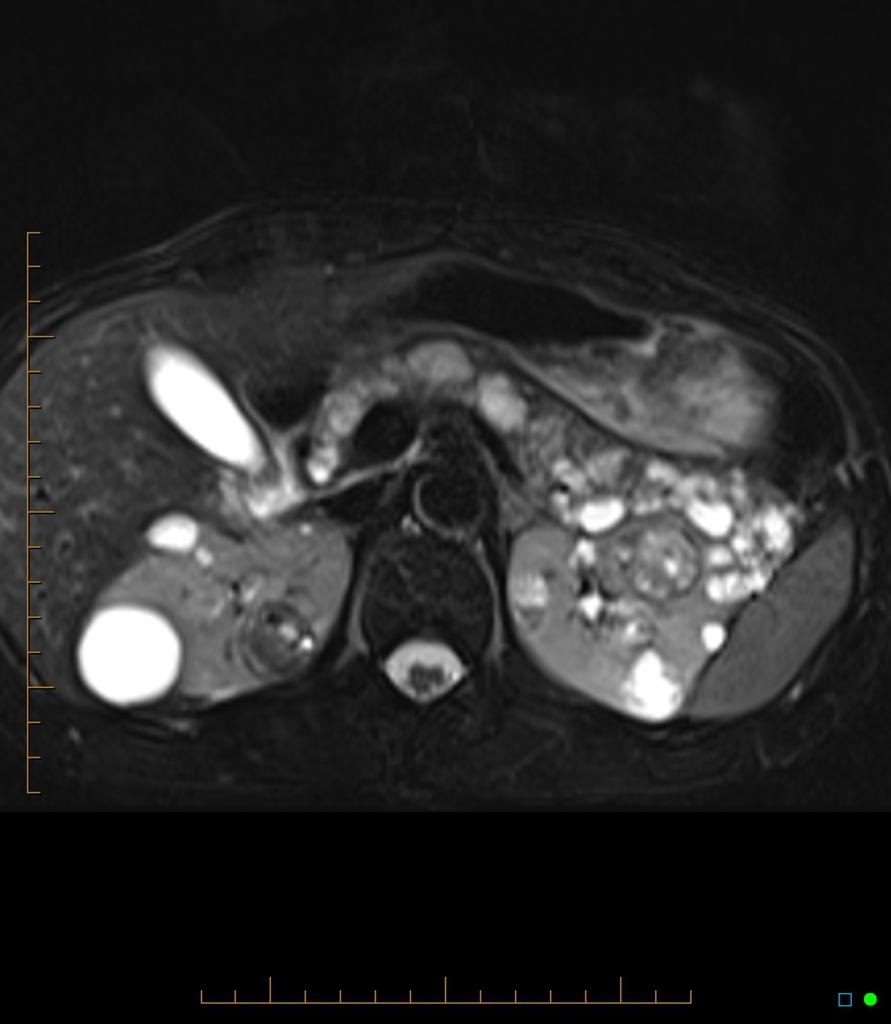

MRI showing renal cysts in patient with known Von Hippel-Lindau syndrome.